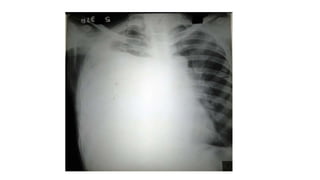

A normal chest x-ray shows the lungs, heart, bones, and soft tissues appearing healthy and unobstructed. The document discusses the different views used in chest x-rays, including PA, AP, lateral, and lateral decubitus views. It also covers topics like depth of inspiration, rotation exposure, the lobes of the lungs, identifying the heart, and how to read a normal chest x-ray.